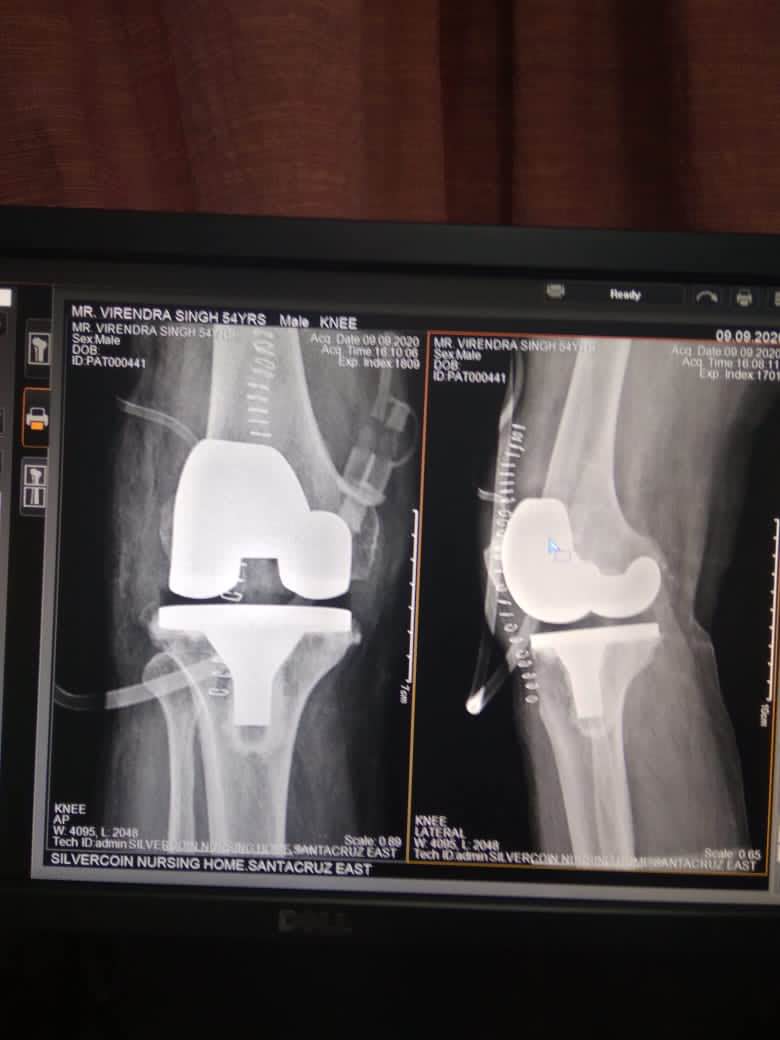

Best KNEE SURGEON in Andheri and Santacruz